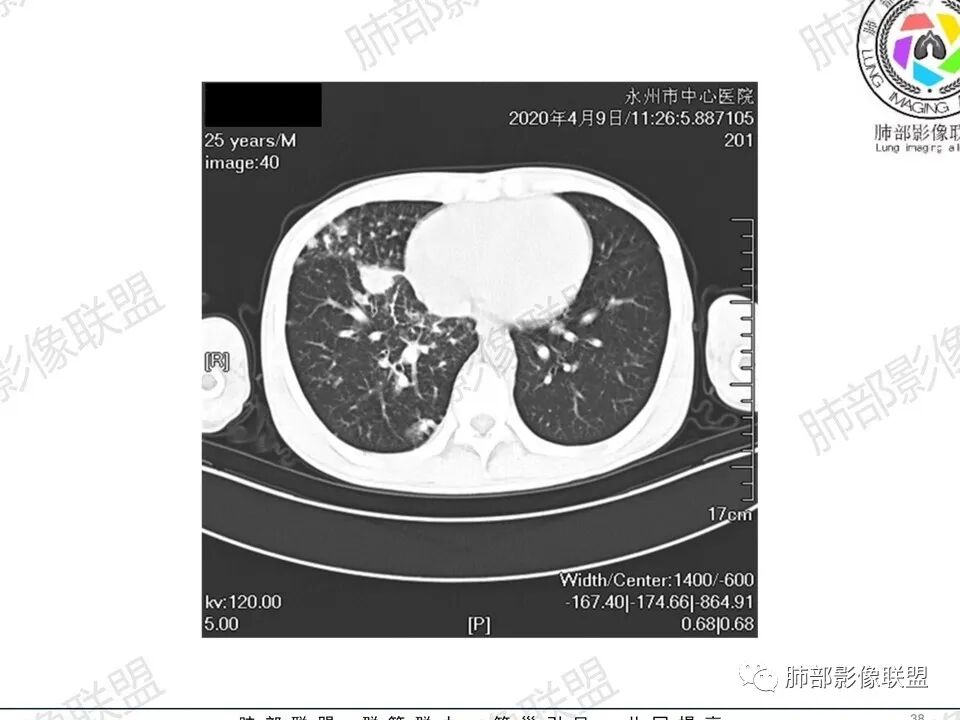

3、影像表现:双肺散在斑片影及结节影,部分结节内可见血管穿行,斑片影沿支气管血管束分布,近胸膜侧病变收缩不明显。部分中央淋巴间质增厚,小叶间隔增厚。病灶内支气管穿行,部分支气管略扩张。局部小结节呈串珠样改变。纵隔、肺门区、锁骨上及腋窝淋淋巴结肿大,部分有融合。心腔低密度。脾大。

2.双肺多发片影及结节影,边界可分辨,右肺中上叶较为密集,没有胸膜下分布优势。病灶实性密度为主,未见钙化及液化。

3.右肺较多微小结节,密度较为浅淡,部分沿血管束分布,未见沿小叶间隔及叶间裂分布结节影,未见典型的终末气道树芽。

4.病灶区域穿行支气管显示良好,未见壁增厚及管腔狭窄。

3.双肺多发结节影,没有明显的新旧不等,没有钙化,微小结节影密度偏低,边缘不够僵硬锐利;病灶区域穿行支气管显示良好,未见壁增厚及管腔狭窄,加之病灶如此广泛,病灶未见收缩、肺叶体积未见缩小,结核中毒症状不明显等等都不支持结核。